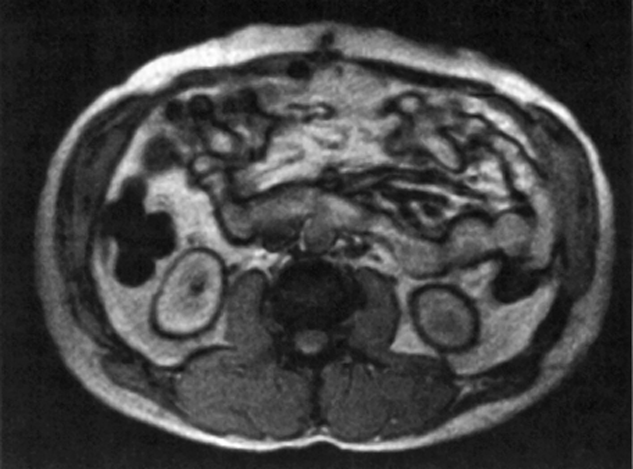

Figure 17-12:

Black boundary artifacts in the abdomen. Gradient-echo sequence with an echo time of 16 ms.